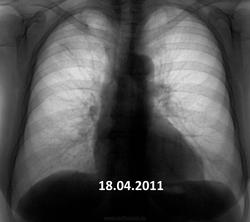

Пожилая опрятная женщина, жалоб нет, просит "отпустить". В феврале фтизиатры написали пневмонию. Сжалился - написал что-то вроде плеврофибрознотакая-то хрень.

Коли фтизиатры отпустили так на них и грех.Сопоставляя с архивом от туберкулёза не отмахнёшся.

Но ведь не может туберкулез меделенно развиваться 4 года?

имеет место. Томографировать надо обязательно.

Не надо сбрасывать со счетов и левую верхушку.

Очень даже может.

Увы! Мне кажется - справа имеет место рецидив. Валентин Львович не зря на левую верхушку обратил внимание.

На первом месте- Tbc.

На втором: Если в легком неясная картина - ищи БАР.

В любом случае ТМГ.

+1. Не пневмония это точно. Прогресс слишком долгий. Больше склоняюсь к онко.

Я за онкологию